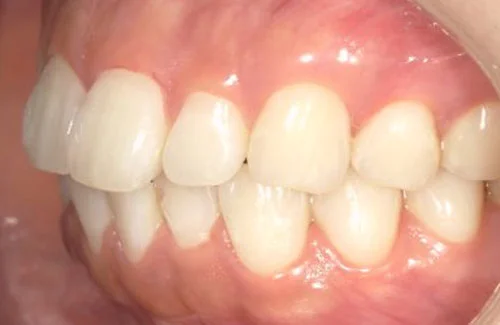

<症例7>歯がガタガタで噛み合わせが悪くお悩み

抜歯無し・マウスピースのみで矯正した症例です。

もともと歯列弓が非常に狭く、V字に近い形をしていたので噛み合わせも非常に不安定でした。

また、下顎前歯部がかなり上の方に生えていたため、下の前歯が上の前歯を突き上げてしまい出っ歯の状態になっていました。

現在では見た目はもちろん、臼歯の噛み合わせも改善しております。

奥歯の患者様も大喜びでした。

患者様と症状

主訴:歯のガタガタ、噛み合わせが悪い

性別・年齢:20代女性

問題点:叢生(重度)、V字歯列弓、ディープバイト

診断:前歯部の叢生を伴うアングルⅠ級、骨格性Ⅰ級の不正咬合

主なリスク:臼歯の移動に伴い一時的に咬合しにくくなる、歯肉退縮

症状:叢生(そうせい) 過蓋咬合(かがいこうごう)

治療内容

治療期間:1年10ヶ月

治療費用:990,000円(税込)

プラン:Full2プラン

抜歯:無し

再診治療費:無し

追加治療費:無し

保定装置費:無し

治療前後の写真